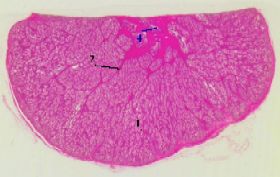

Препарат 50.

Предстательная железа собаки. Окраска гематоксилин-эозином.

1. а) Простата - один из органов мужской половой системы.

б) Она представляет собой

совокупность отдельных желёзок (1),

окружённых мышечно-

эластической стромой (2)

.

а) (Малое увеличение)

1. Строма (2) расходится от уретры прослойками:

крупные прослойки разделяют простату на дольки,

а мелкие проникают внутрь долек, окружая отдельные железы.

1. а) Многочисленные железы простаты являются

по характеру секрета - слизистыми,

а по форме концевых отделов (1) -    альвеолярно-трубчатыми.

б) Причём, эти отделы

сильно разветвлены.

2. Сочетание разветвлённых желёз и многочисленных прослоек придаёт препарату простаты

характерный папоротникообразный вид.